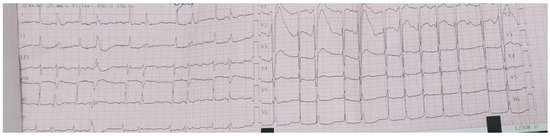

4.2. Diagnostic Findings: Mitral Valve Dysfunction and Embolic Phenomena

4.3. Coronary Complications and Diagnostic Dilemma